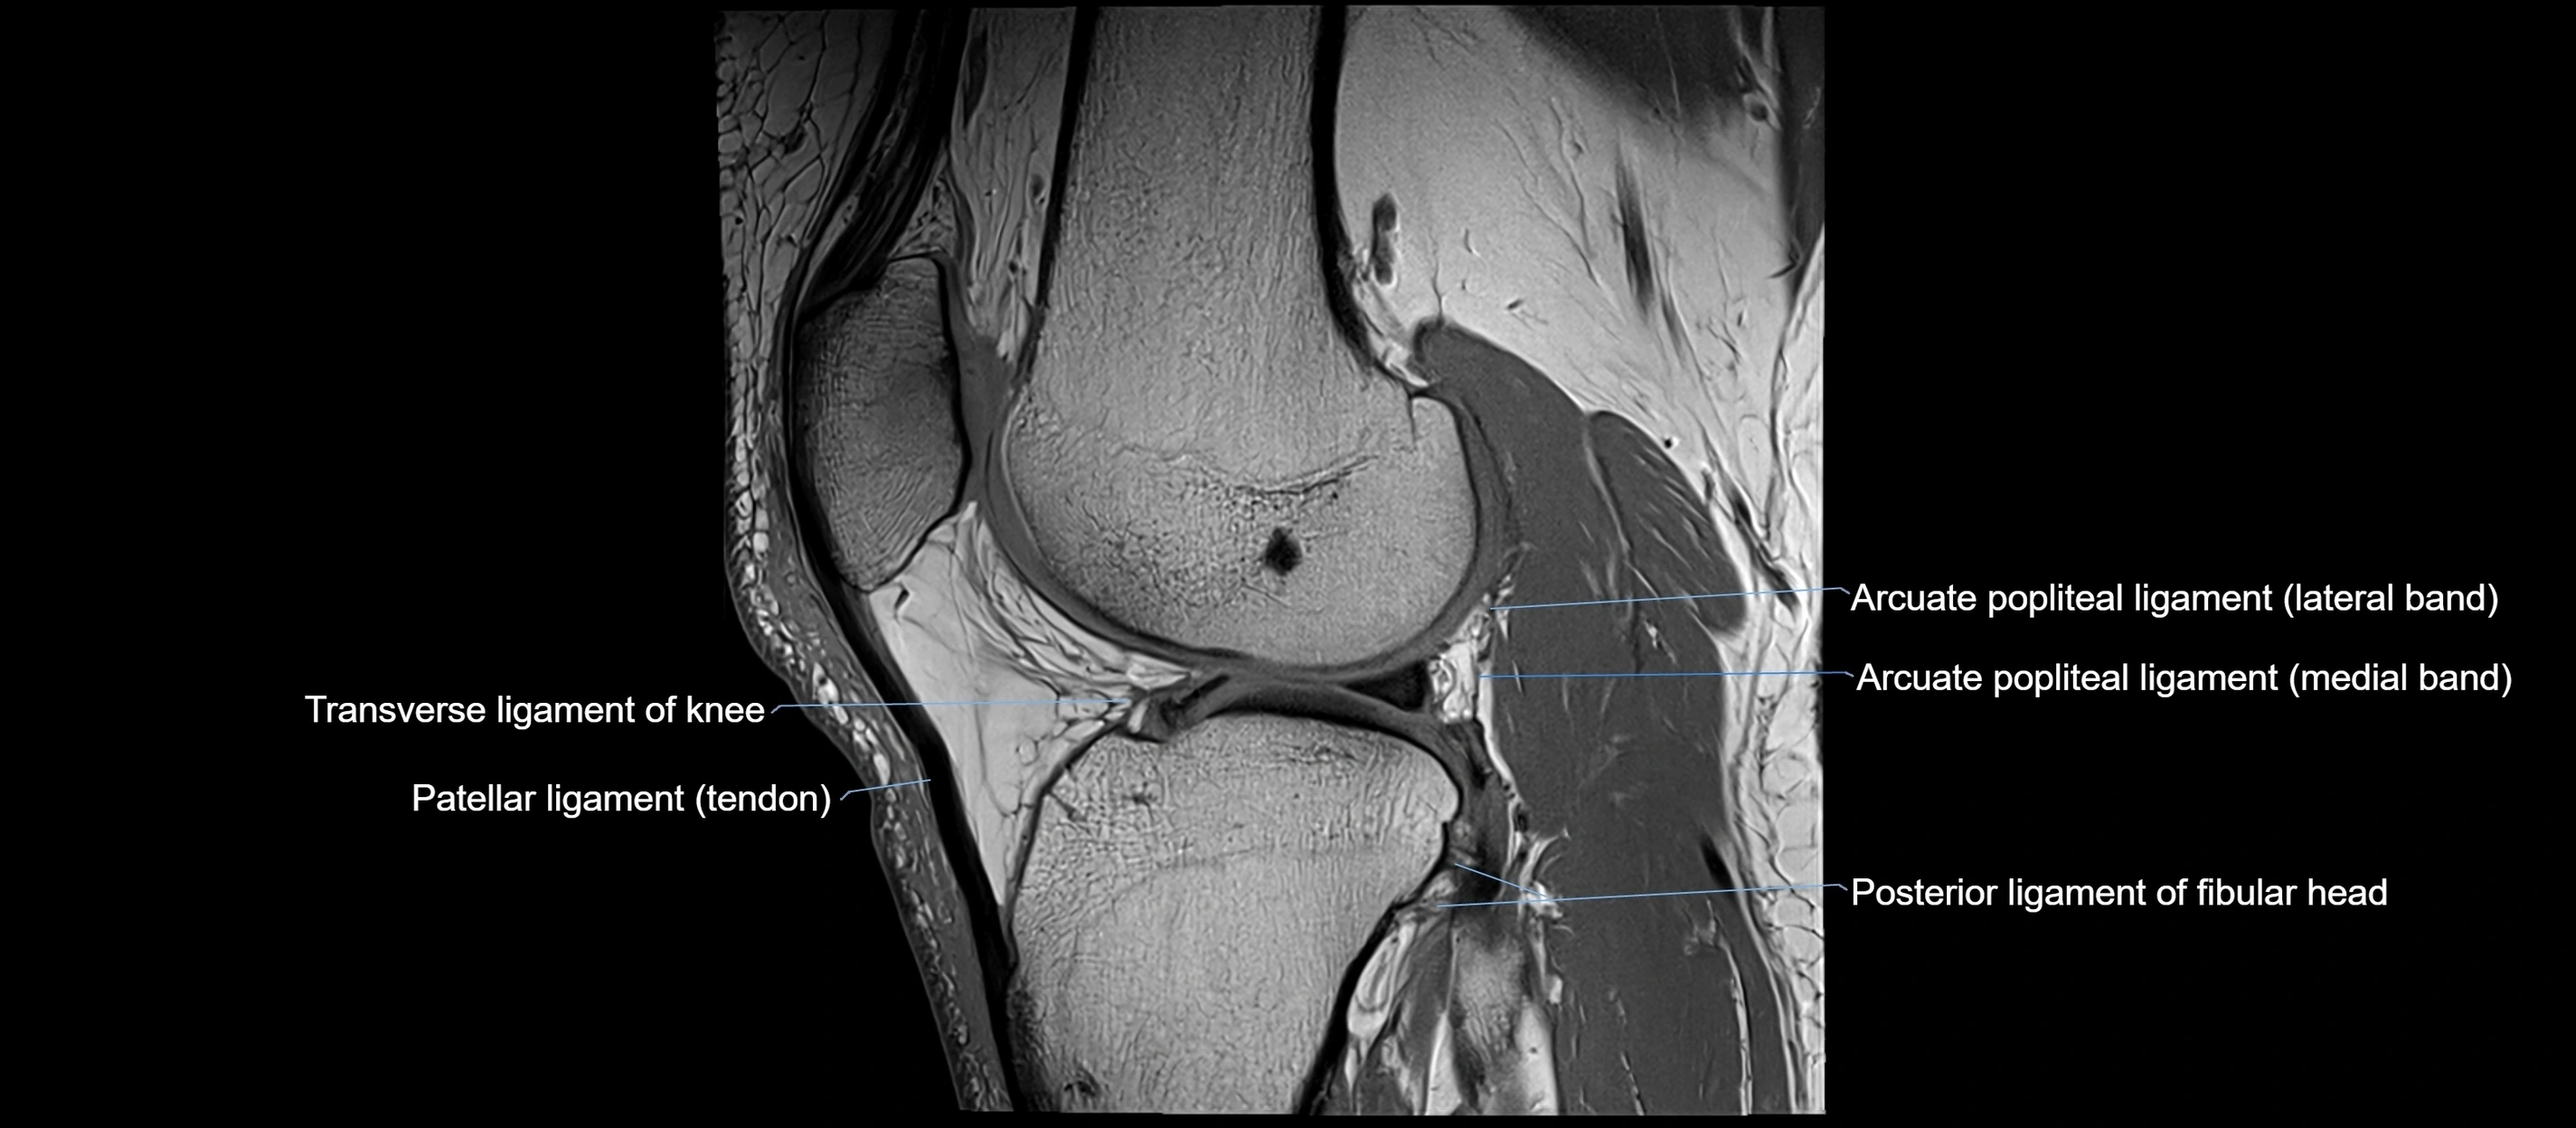

MRI images

image